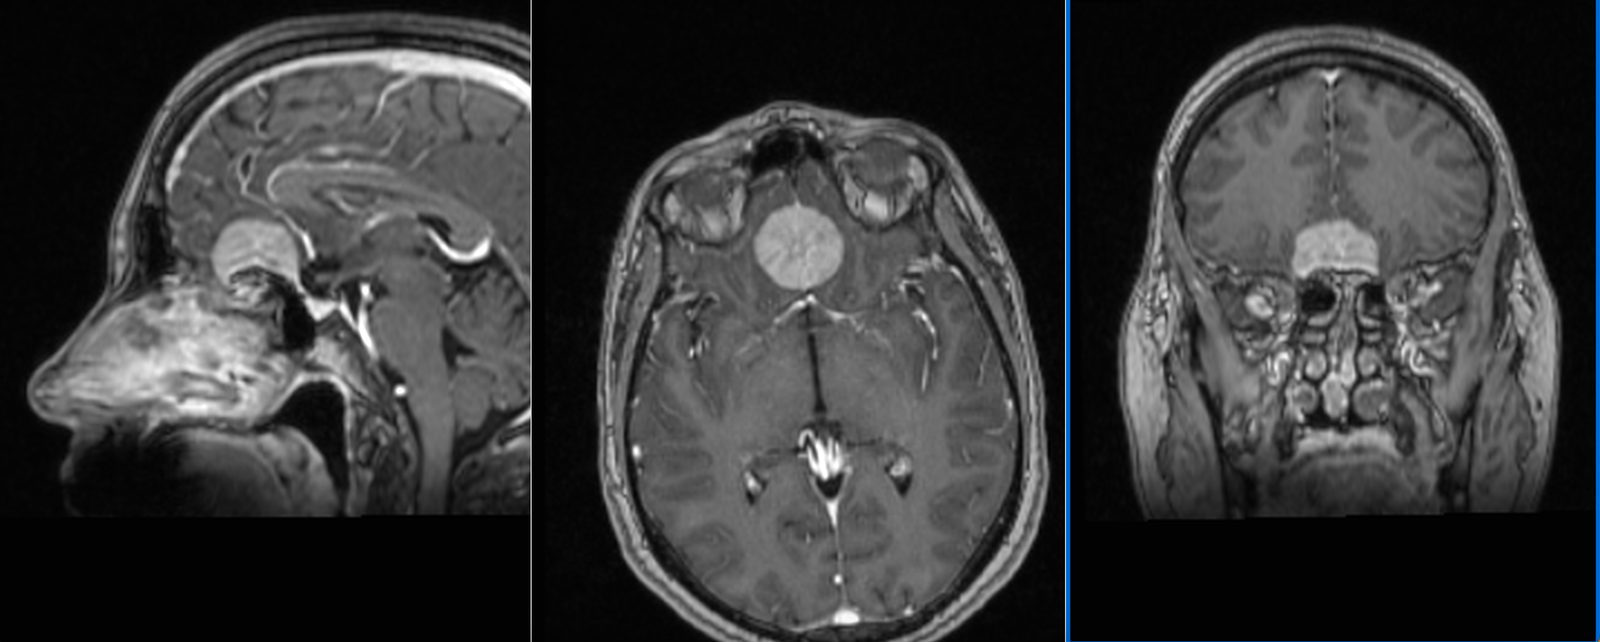

Meningiom olfactiv – RMN preoperator

Meningiom olfactiv – RMN postoperator

- RMN – cea mai completă investigație, oferă detalii despre relația cu țesutul cerebral, vasele de sânge și nervii Captarea substanței de contrast este deosebit de importantă.

Meningiom de tubercul selar